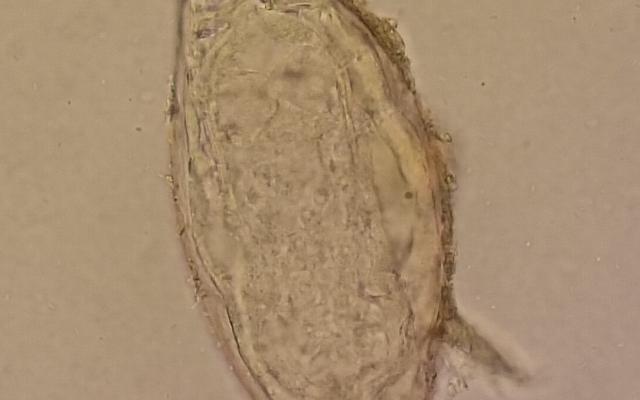

Dit artikel is alleen beschikbaar als PDF.Lees de PDF Artikelinformatie Online verschenen op 25 februari 1979 Citeer dit artikel als Ned Tijdschr Geneeskd. 1979;123:928-33 Heb je nog vragen na het lezen van dit artikel? Check onze AI-tool en verbaas je over de antwoorden. ASK NTVG Ook interessant Beeldquiz Rugpijn, krachtverlies en eieren in de feces Diagnose in beeld Een man met pijn en krachtsverlies in de benen Stand van zaken Behandeling van pijn en slapeloosheid Meer gerelateerd … Reacties Login om een reactie te plaatsen